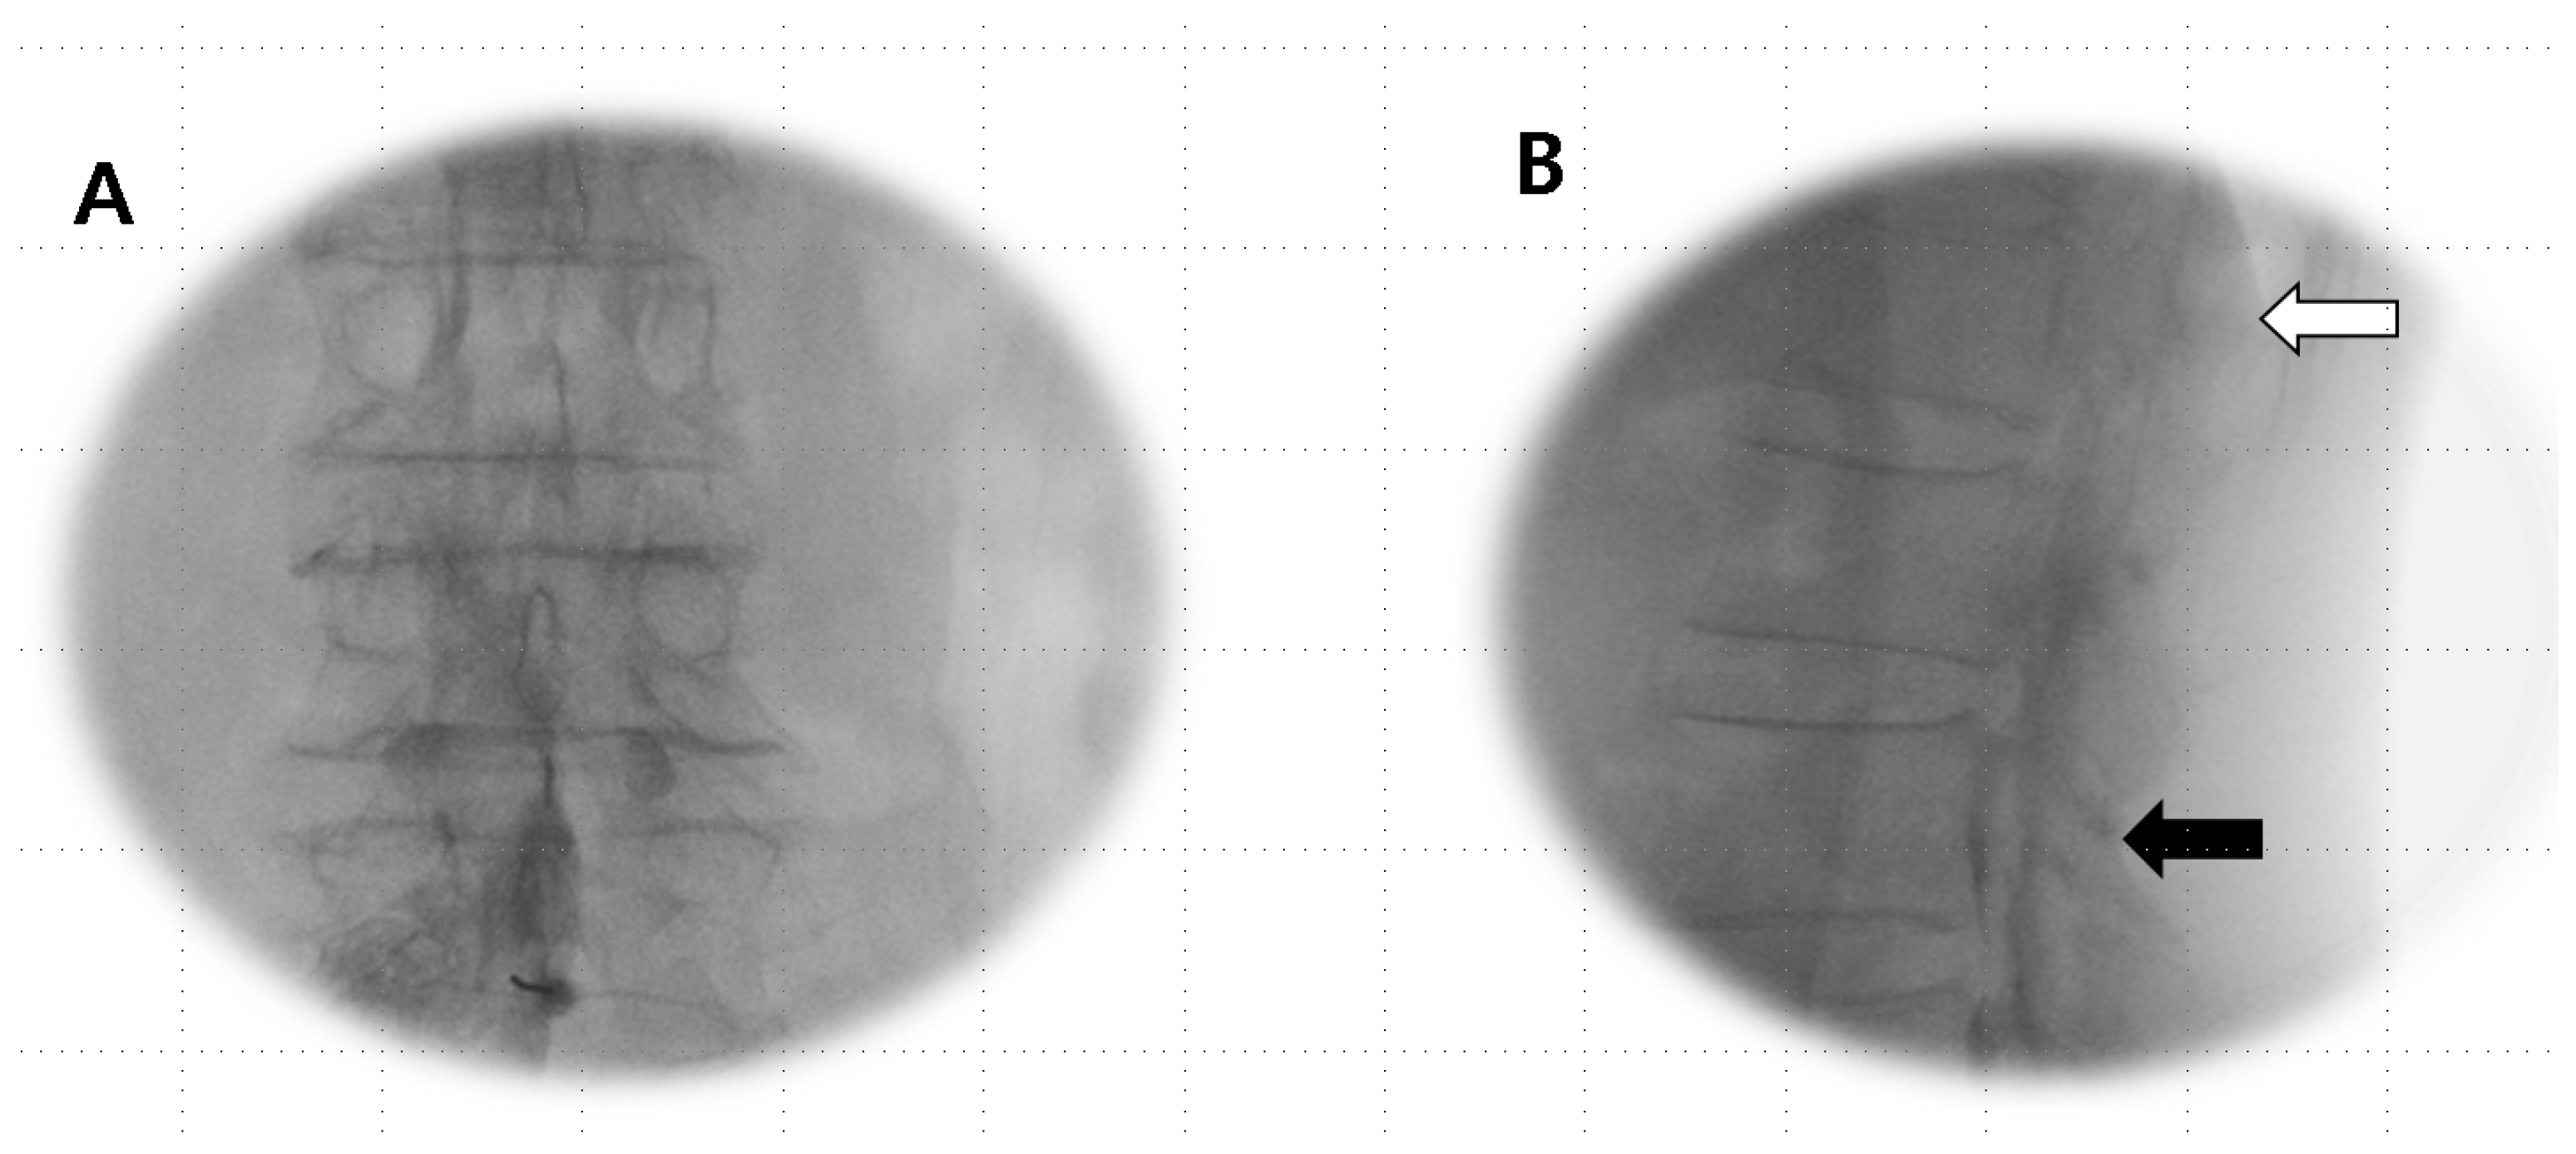

Anesthetics were administered if the Tuohy needle tip was situated within the epidural or subdural space (Figure 1A,B) or straddled between both spaces (Figure 2A,B).

Figure 2.

Combined epidural–subdural image. (A) AP view: imaging shows a thick, sausage-like mass of subdural contrast that transitions into a less dense epidural radiopaque image along the exiting nerve root, with the flow observed moving cranially. (B) Lateral view: the imaging reveals a progression from two thickened anterior–posterior columns positioned medially in the lower region (black arrow), transitioning to thinner, more peripheral anterior–posterior tracts (open arrow) that become more apparent in the epidural image as they flow cranially.